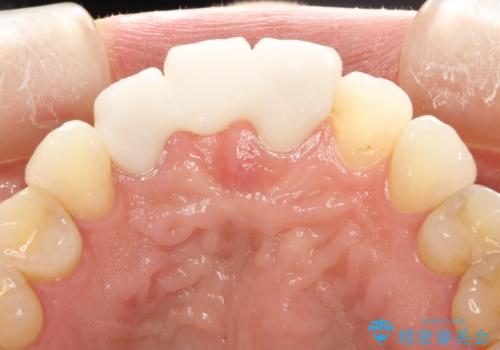

古いかぶせ物は土台ごと歯から脱落してしまっており、歯の内面には複数の亀裂が入っている状態でした。残存歯質が非箔であることと、動揺の程度から、やむを得ず抜歯→ブリッジという方法を選択していただき、歯根挺出を用いることでなるべく前歯の骨の陥没を防ぎ、ブリッジを製作しました。

かぶせ物の種類:PFZ standard